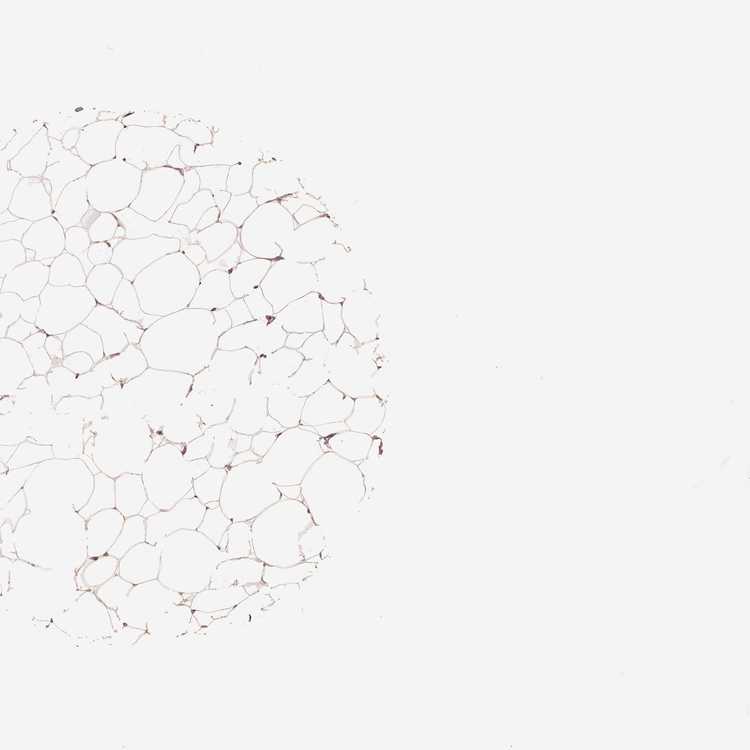

BREAST - Antibody stainingi

Antibody staining in the annotated cell types in the current human tissue is reported as not detected, low, medium, or high, based on conventional immunohistochemistry profiling in selected tissues. This score is based on the combination of the staining intensity and fraction of stained cells.

Each image is clickable and will lead to virtual microscopy that enables deeper exploration of all samples and also displays staining intensity scores, fraction scores and subcellular localization as well as patient and tissue information for each sample.

Antibody HPA071562

Adipocytes Low

Glandular cells Not detected

Myoepithelial cells Not detected